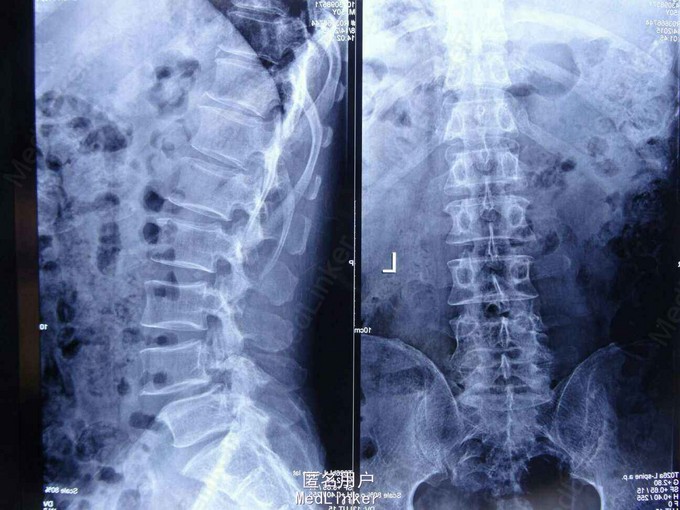

患者男性,55岁,缘于1个月前无明显诱因出现活动后腰部麻木、疼痛,呈持续性钝痛,行走后麻木、疼痛明显,并波及右下肢,休息后不能缓解,严重影响日常生活及睡眠。患者为求系统诊治就诊于我院,门诊医师经仔细询问病史、查体、阅腰椎MRI后,以“腰4椎体滑脱(I度)、腰椎管狭窄(L4-5)”收入院。此次病程中,患者无头晕、头痛,无发热、盗汗,无腹胀、腹泻,饮食、睡眠欠佳,大、小便正常

查体: 跛行步态,腰部活动明显受限。腰4、5棘突压痛及叩击痛(+),伴右下肢放散痛,疼痛沿右大腿后方放散至小腿外侧;右下肢感觉减退,余肢体感觉未见明显异常;右下肢大腿、小腿抬腿肌力V级、右踝关节背伸肌力IV级、右足趾背伸肌力V级、左下肢肌力V级;四肢肌张力正常;双下肢直腿抬高试验阴性,双侧Babinski征阴性。VAS:5分;JOA:7分;ODI:62%。 腰椎MRI: 腰4椎体略向前移位,腰4-5椎管明显狭窄。

诊断: 腰4椎体滑脱(I度)、腰椎管狭窄(L4-5) 治疗原则: 择期手术治疗。于全麻下行腰椎后路切开复位植骨融合内固定术,术后给予抗炎、营养及对症治疗。